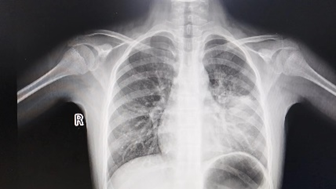

此图片来源于网络,如有侵权,请联系删除

肺炎支原体肺炎的影像学表现